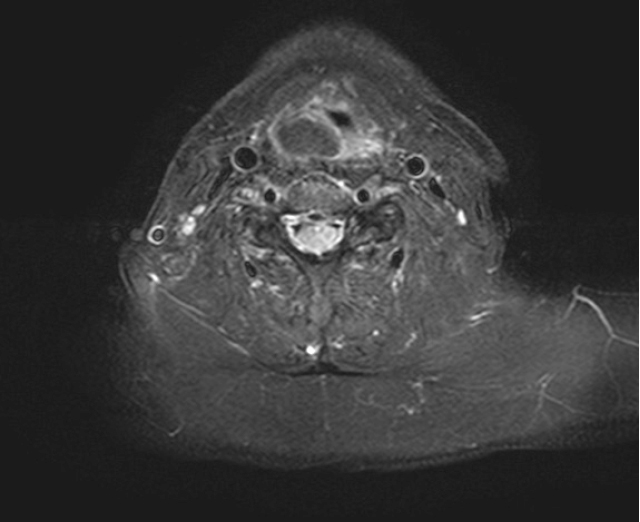

頸部MRI:右梨状窩付近に境界明瞭な24mm大の腫瘤を認める.腫瘤はT1及びT2強調画像で高信号(Figure 3,4),脂肪抑制T1強調画像で低信号を呈し(Figure 5),著明な拡散異常や内部造影効果は認めなかった.

MRI T1強調,水平断像.腫瘤は境界明瞭で高信号を呈する.